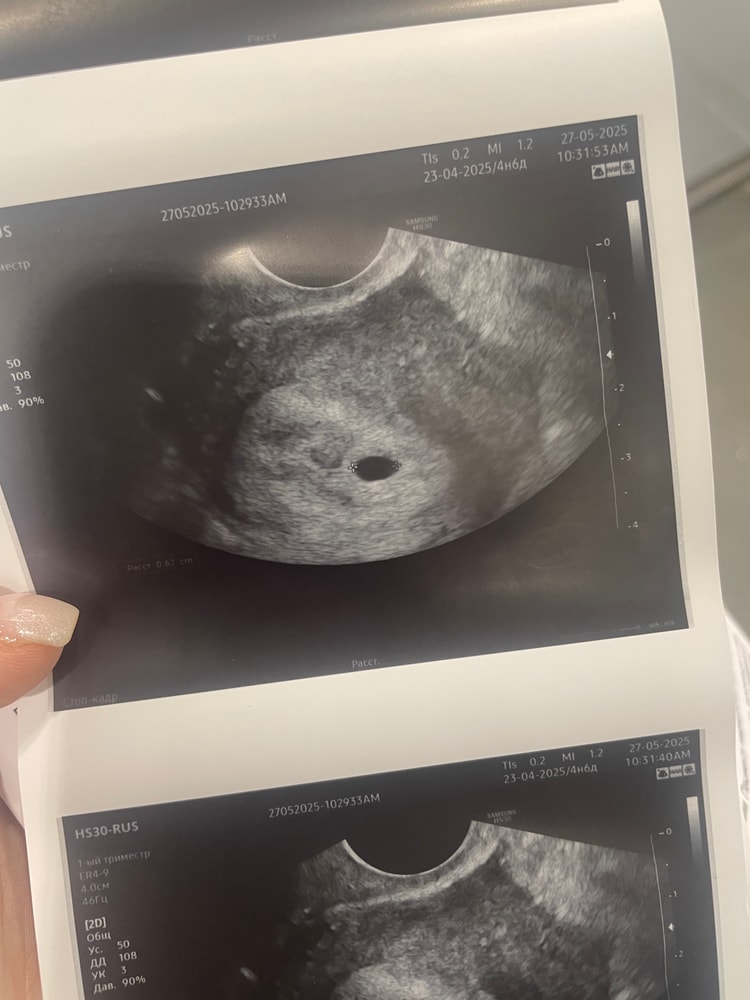

Сдаю Хгч в динамике. Сегодня 3 раз сдала. Ниже предыдущие 2 раза⬇️

27дц-227,7

29дц-493,9

в день сдачи второго раза у меня все перестало болеть резко. Грудь намного меньше болит. Если только прощупывать - то немного неприятно. Живот не тянет почти, нет таких тянущих ощущений как это было на 27дц.

девочки, поделитесь как у вас было) Нужна поддержка

Пришел результат хгч 227,7. Дц 27